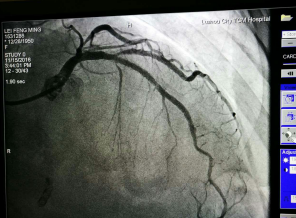

为求明确诊断及进一步治疗,周阿姨慕名来到了我院心血管内科住院诊治。经冠状动脉造影检查,发现原来植入的支架发生了99%的狭窄,即支架内再狭窄,这就是导致她目前再次出现活动后胸闷胸痛的根本原因。

术前